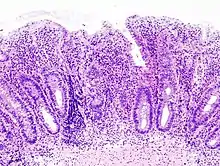

H&E stain of a colonic biopsy showing a crypt abscess, a classic finding in ulcerative colitis

Biopsy sample (H&E stain) that demonstrates marked lymphocytic infiltration (blue/purple) of the intestinal mucosa and architectural distortion of the crypts.

Crypt abscess. H&E stain.

Biopsies of the mucosa are taken during endoscopy to confirm the diagnosis of UC and differentiate it from Crohn's disease, which is managed differently clinically. Histologic findings in ulcerative colitis includes: distortion of crypt architecture, crypt abscesses, and inflammatory cells in the mucosa (lymphocytes, plasma cells, and granulocytes).[28] Unlike the transmural inflammation seen in Crohn's disease, the inflammation of ulcerative colitis is limited to the mucosa.[28]